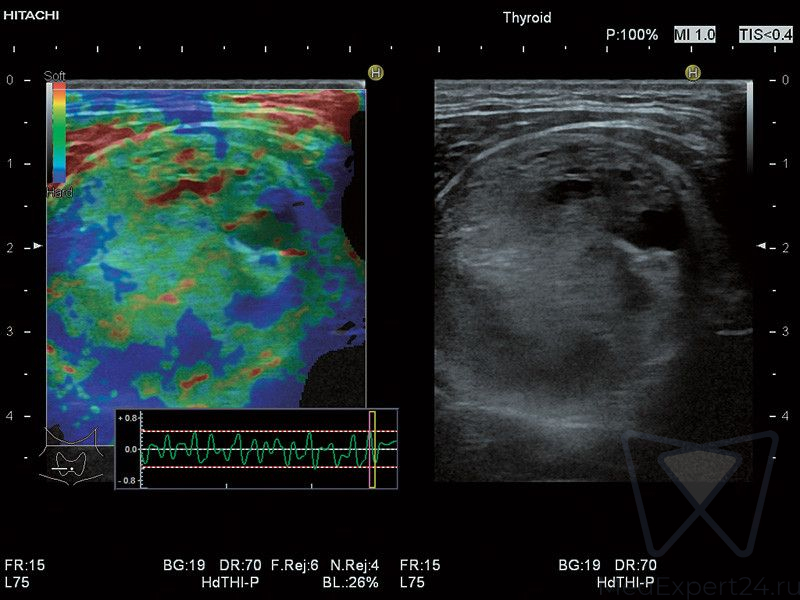

Ультразвуковая система HI VISION Ascendus является кульминацией длительного сотрудничества большой сети исследовательских лабораторий корпорации Hitachi. Благодаря усердной работе опытных профессионалов, стало возможным воплотить самые передовые технологии в УЗИ аппарате экспертного класса.

Расширенные возможности визуализации:

- HI-RTE эластография в режиме реального времени,